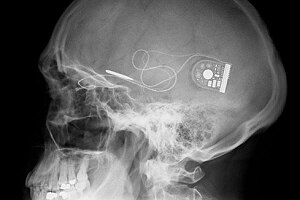

(Left) Implant behind eye. (Right) Retinal scan showing the sensor chip in place. (via University of Oxford)

X-ray image of the complete system installed into Chris James. (via University of Oxford)

The implant is a 3mm square chip containing 1,500 light sensitive diodes. The chip is attached to the back of the eye where a signal can be sent between electrodes and the patient's optical nerves. The system is powered by an implanted power supply buried behind the ear, similar to some cochlear devices. Professor MacLaren explained that the sensor will "stimulate the overlying nerves to create a pixellated image." He continued, "Apart from a hearing aid like device behind the ear, you would not know a patient had one implanted. We are all delighted with these initial results. The vision is different to normal , and it requires a different type of brain processing. We hope, however, that the electronic chips will provide independence for many people who are blind from retinitis pigmentosa."